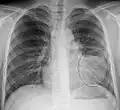

- Normal AP CXR

Normal lateral CXR